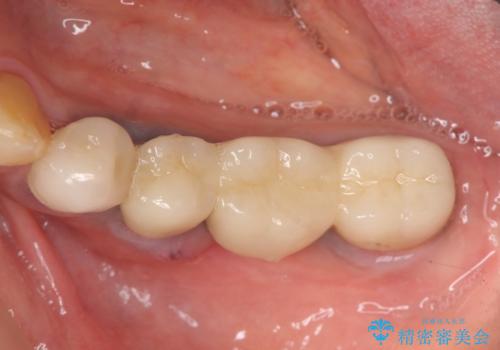

- 100万円(ストローマンインプラント×2・仮歯×4・チタンカスタムアバットメント×2・ジルコニアクラウン×4)費用は治療当時の料金となります

ブリッジ治療は支台となる歯が弱いと、今回のように周囲の骨が吸収したり歯が割れてしまったりといったトラブルがおきます。咬合力に対抗するため、今回はインプラントを用いて機能回復を行いました。